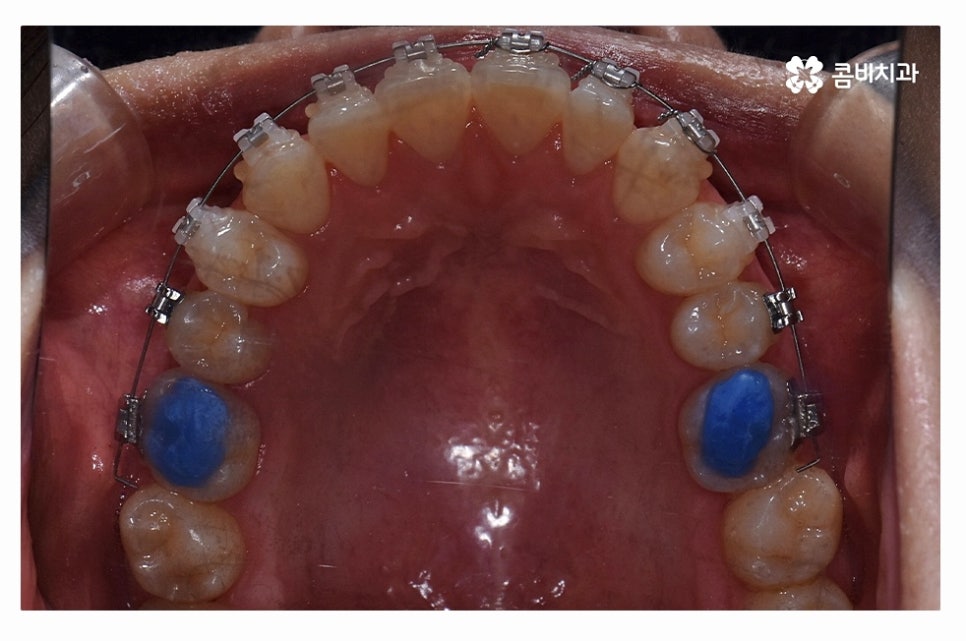

오늘 보여드릴 사례도 덧니교정이 비발치로 진행이 된 사례이며

치아의 이동 공간과 치아 상태, 골격, 얼굴형 등을

종합적으로 판단할 때 비발치로도 진행이 가능했던 사례라고 할 수 있어요.

교정 장치의 선택에 있어서는 다양한 교정 장치의 선택이 가능한데

심미성이 강조된 설측교정부터 콤비교정,

위 환자분의 사례처럼 클리피씨교정이 보편적으로 많이 활용되고 있는데요.

클리피씨교정은 치아의 이동이 일반 장치에 비해 상대적으로

빠르기 때문에 치료 기간이 단축될 수 있으며

통증의 감소, 내원 횟수를 줄일 수 있다는 장점 등이 있어요.